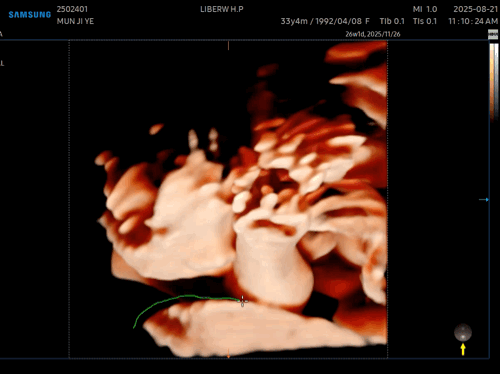

아쉽게도

사탕이는 얼굴을 가리고 있었다🥲

사탕아~~ 코만 구경하라는 거니~~~?

얼굴은 숨어버리고

손이랑 발만 보여줌 ㅎㅎㅎㅎㅎ

그것도 웅크리고 숨어있어서

손이랑 발도 제대로 못 찍고,,,

다음 주에 다시 오기로 하고 끝냈다😊